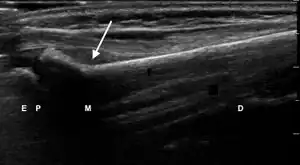

| 3 | Cortical Break Fracture | "Broken" | Break, step or gap in bone cortex which appears as a black zone in the bright, sharp white line[10][11][14][15][16] | ![]() Ultrasound dorsal view of cortical break fracture of radius (shown by arrow). E = epiphysis; P = physis; M = metaphysis; D = diaphysis. |